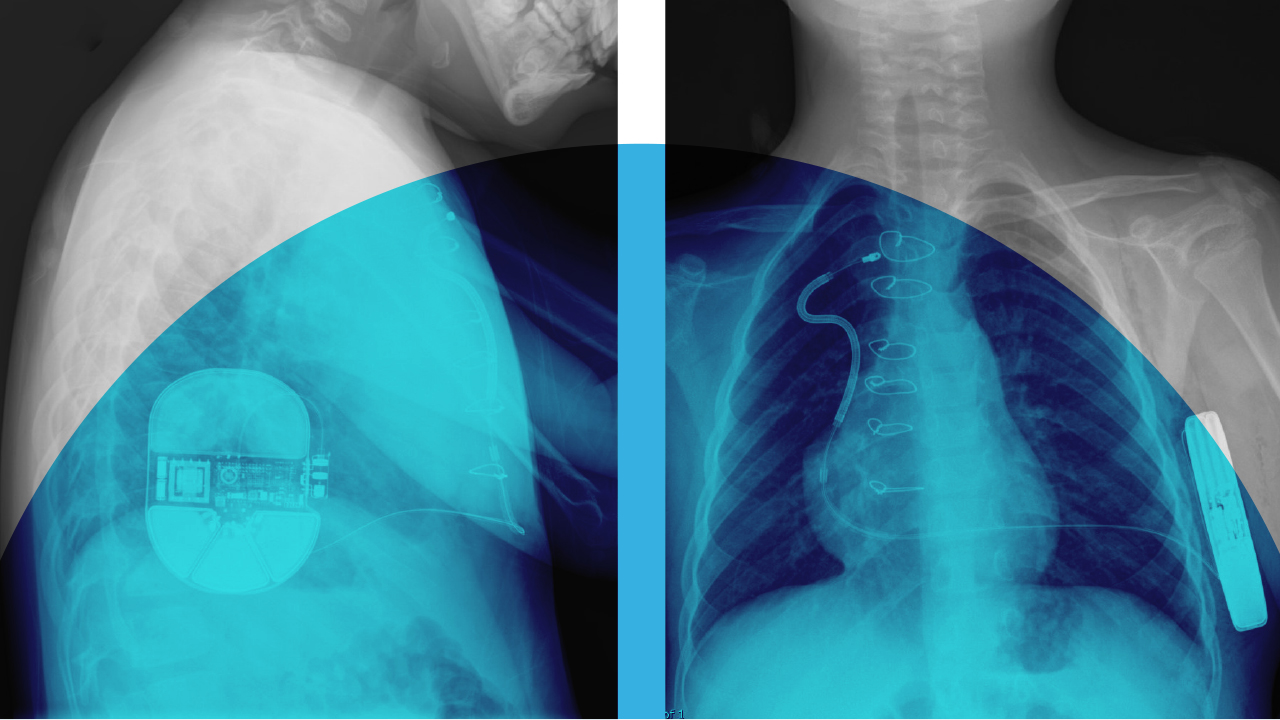

Having a permanent device implanted in your body is a big step for anyone — especially children. For pediatric patients with congenital heart disease (e.g., tetralogy of Fallot or hypertrophic cardiomyopathy) or those with an inherited arrhythmia syndrome (e.g., long QT syndrome or Brugada syndrome), there are two primary options available — transvenous implantable cardioverter defibrillators (TV-ICDs) and subcutaneous ICDs (S-ICDs). While S-ICDs are less invasive, researchers set out to determine how safe and effective they are compared to TV-ICDs among pediatric patients.

For more than 40 years, TV-ICDs have been the gold standard for treating life-threatening heart rhythms, but they are not without drawbacks. For one, they are more invasive with leads running through a vein and directly into the heart. Despite decades of advances in transvenous lead technology, there are still complications with lead fractures and device-associated endocarditis. Though the risk for infection over the lifetime of a device is relatively low (about 2% to 3%), any device infection has to be treated as if it involves the heart tissue as well. Additionally, as scar tissue forms between the vessel walls and the lead itself, replacing leads becomes much more difficult.

S-ICDs were approved by the FDA over ten years ago and were designed as a disruptor to reduce lead-related complications and minimize the risks associated with systemic infections and device extraction. Although a bit larger, S-ICDs are implanted under the skin at the side of the chest and connect to a lead that runs along the ribs and breastbone but does not attach to the heart itself. Early studies demonstrated the safety and efficacy of S-ICDs in adults, but widespread adoption in children has been slow — potentially due to a lack of clear guidelines and studies on effectiveness.